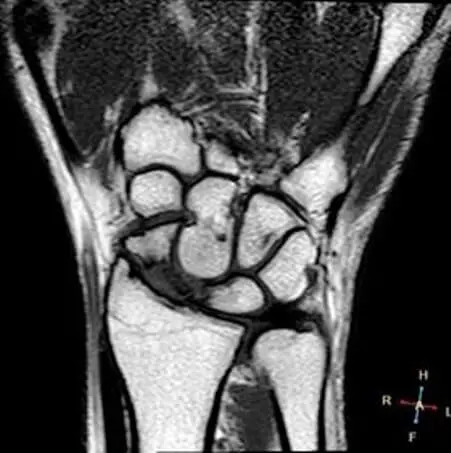

МРТ лучезап’ястного суглоба

МРТ лучезап’ястного суглоба – одна зі складних маніпуляцій. Сам суглоб складний.

Більш того, для дослідження лучезапястного суглоба потрібна спеціальна МРТ котушка (це – частина МРТ апарату, яка призначена спеціально для МРТ дослідження лучезапястного суглоба і кисті ). Повний набір котушок, включаючи котушки для дослідження лучезапястного суглоба і кисті є в Центрі «Меддіагностика».

МРТ кисті

Ексклюзивне МРТ дослідження, особливо важливе при травмі кисті. Читати більше про МРТ кисті .